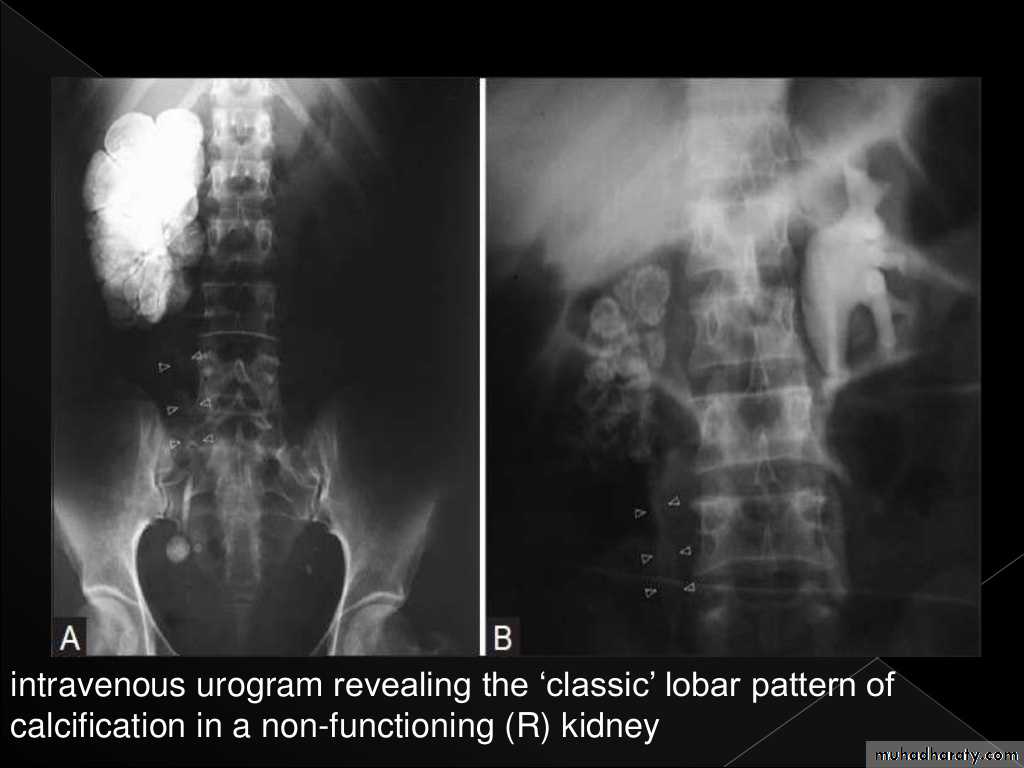

Plain films may show large globular, amorphous calcificationsIVU :

Cortical scarring

"Smudged" papillae (moth-eaten) –irregular due to inflammation and necrosis

Infundibular strictures

Hydrocalyces without dilatation of renal pelvis, or Hydronephrosis

Autonephrectomy – small, shrunken kidney with dystrophic calcification